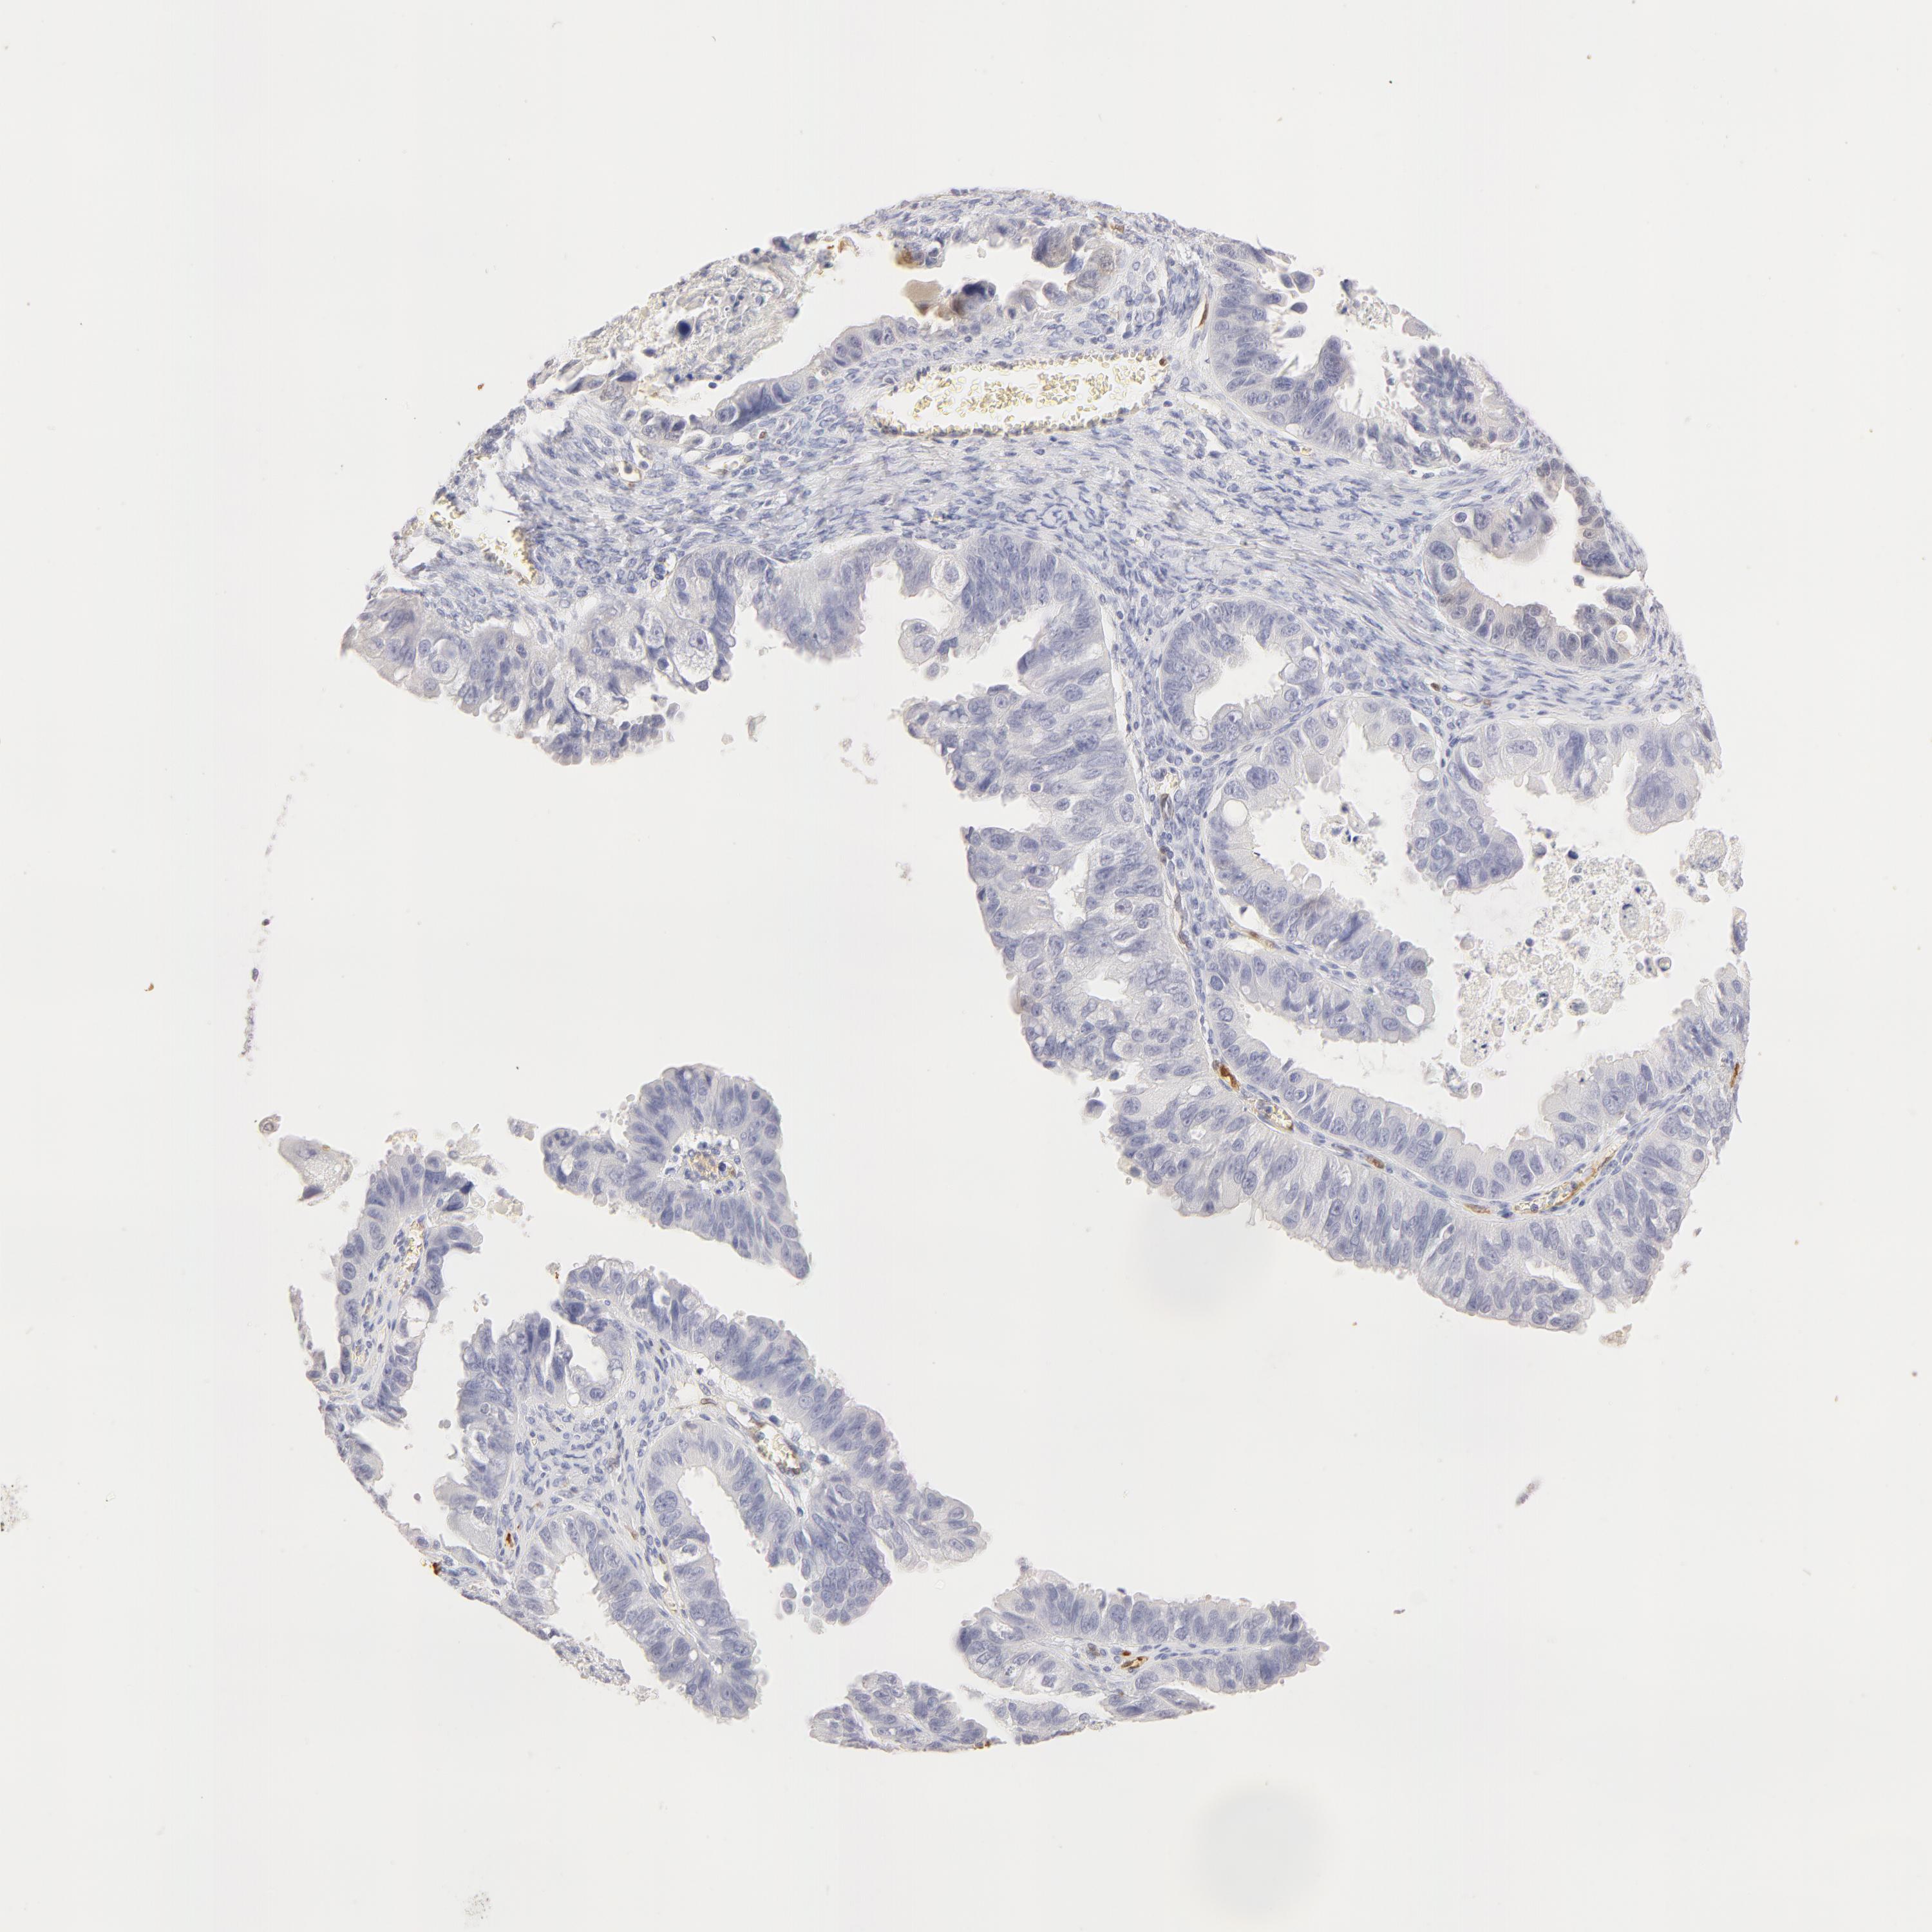

OVARIAN CANCER - Protein expressioni

A mouse-over function shows sample information and annotation data. Click on an image to view it in a full screen mode. Samples can be filtered based on level of antibody staining by selecting one or several of the following categories: high, medium, low and not detected. The assay and annotation is described here.

Note that samples used for immunohistochemistry by the Human Protein Atlas do not correspond to samples in the TCGA dataset.

Antibody stainingi

Antibody staining in the annotated cell types in the current human tissue is reported as not detected, low, medium, or high, based on conventional immunohistochemistry profiling in selected tissues. This score is based on the combination of the staining intensity and fraction of stained cells.

Each image is clickable and will lead to virtual microscopy that enables deeper exploration of all samples and also displays staining intensity scores, fraction scores and subcellular localization as well as patient and tissue information for each sample.

Antibody HPA001550

Antibody CAB010102

Carcinoma, endometroid

Cystadenocarcinoma, serous, NOS

Cystadenocarcinoma, mucinous, NOS

Carcinoma, NOS